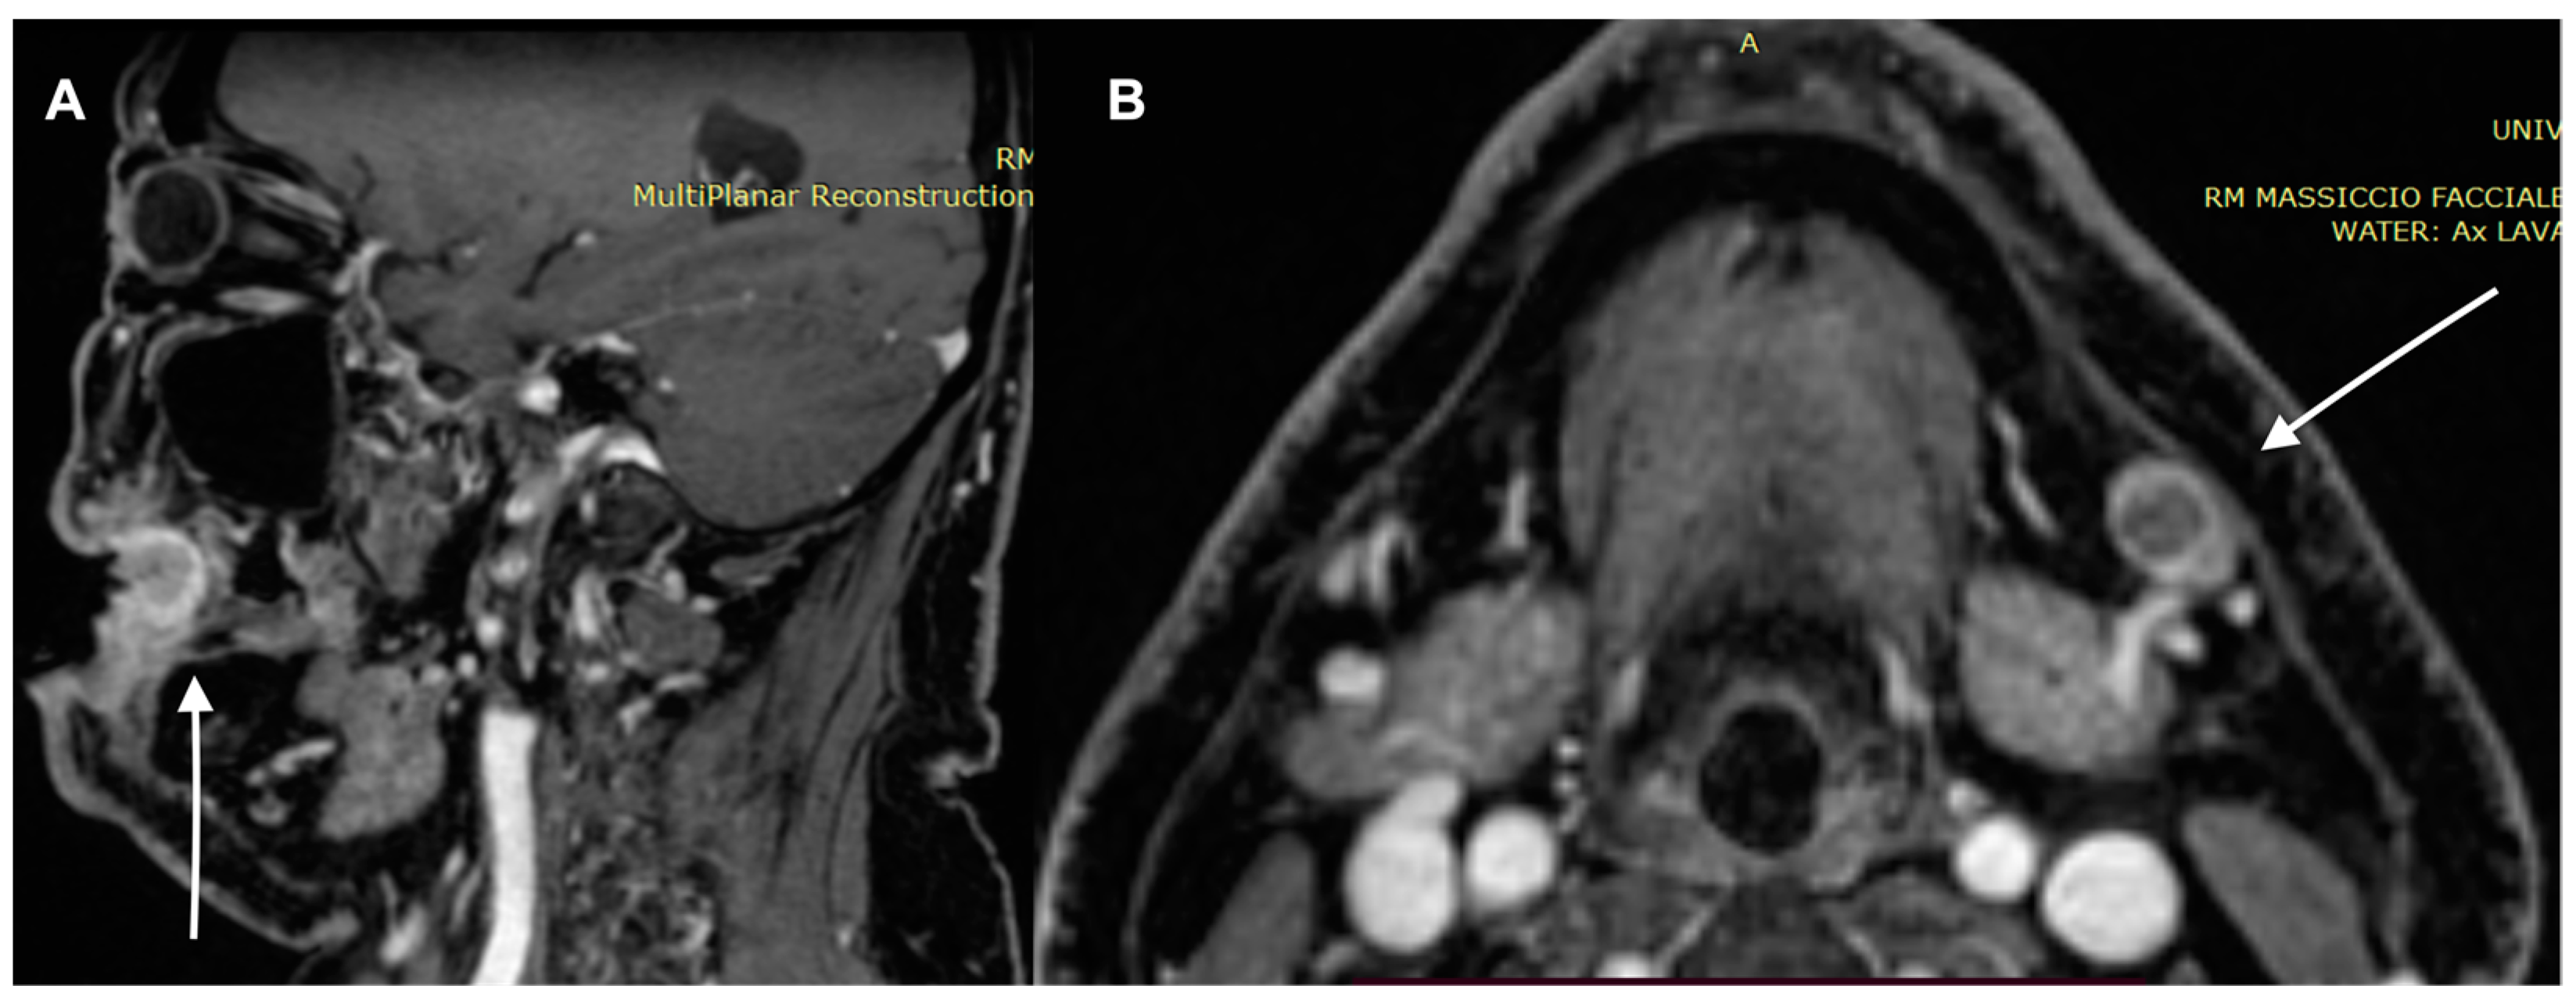

- Kawaguchi, M.; Kato, H.; Noda, Y.; Kobayashi, K.; Miyazaki, T.; Hyodo, F.; Matsuo, M. Imaging findings of malignant skin tumors: Radiological–pathological correlation. Insights Imaging 2022, 13, 52. [Google Scholar] [CrossRef] [PubMed]

- Kawaguchi, M.; Kato, H.; Suzui, N.; Miyazaki, T.; Tomita, H.; Hara, A.; Matsuyama, K.; Seishima, M.; Matsuo, M. Imaging findings of cutaneous angiosarcoma of the scalp: Comparison with cutaneous squamous cell carcinoma. Neuroradiol. J. 2021, 34, 329–334. [Google Scholar] [CrossRef]

- Kawaguchi, M.; Kato, H.; Tomita, H.; Hara, A.; Suzui, N.; Miyazaki, T.; Matsuyama, K.; Seishima, M.; Matsuo, M. Magnetic Resonance Imaging Findings Differentiating Cutaneous Basal Cell Carcinoma from Squamous Cell Carcinoma in the Head and Neck Region. Korean J. Radiol. 2020, 21, 325–331. [Google Scholar] [CrossRef] [PubMed]

- Sheng, M.; Tang, M.; Lin, W.; Guo, L.; He, W.; Chen, W.; Li, K.; Liu, J.; Xiao, C.; Li, Y. The value of preoperative high-resolution MRI with microscopy coil for facial nonmelanoma skin cancers. Ski. Res. Technol. 2021, 27, 62–69. [Google Scholar] [CrossRef]

- Juan, Y.-H.; Saboo, S.S.; Tirumani, S.H.; Khandelwal, A.; Shinagare, A.B.; Ramaiya, N.; Krajewski, K.M. Malignant Skin and Subcutaneous Neoplasms in Adults: Multimodality Imaging With CT, MRI, and 18F-FDG PET/CT. Am. J. Roentgenol. 2014, 202, W422–W438. [Google Scholar] [CrossRef]